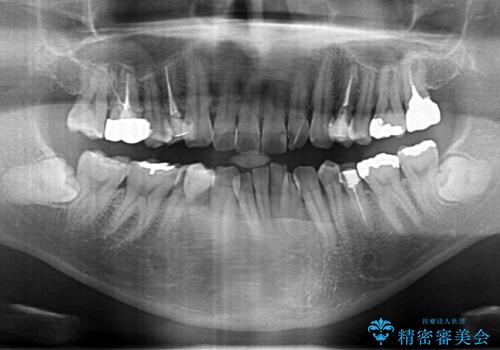

- 今装着されている全ての銀歯の除去、虫歯の治療、矯正治療を含めた総合治療を希望され来院されました。

放置すると大きくなりそうな虫歯をまず治療、矯正治療を行ったのち、全ての銀歯を除去しセラミック治療を行う治療計画としました。